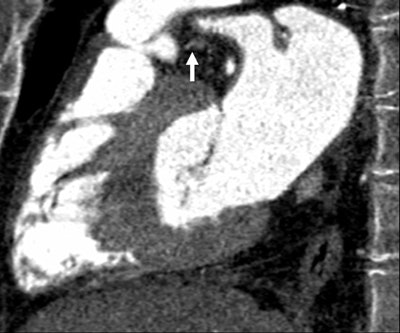

| Images 1-7 shown top to bottom: A 59-year-old man presented with atypical chest pain. A circumscribed, short-segment high-degree stenosis (arrow) in the proximal LAD is difficult to detect on transverse (1), sagittal (2), or coronal (3) multiplanar reformats. Use of advanced visualization tools with automated extraction of the coronary artery tree (4) and automated display as curved multiplanar reformat (5) clearly identifies the lesion, also seen in the 3D view (6) and confirmed on conventional catheter angiography (7). All images courtesy of Dr. U. Joseph Schoepf. |